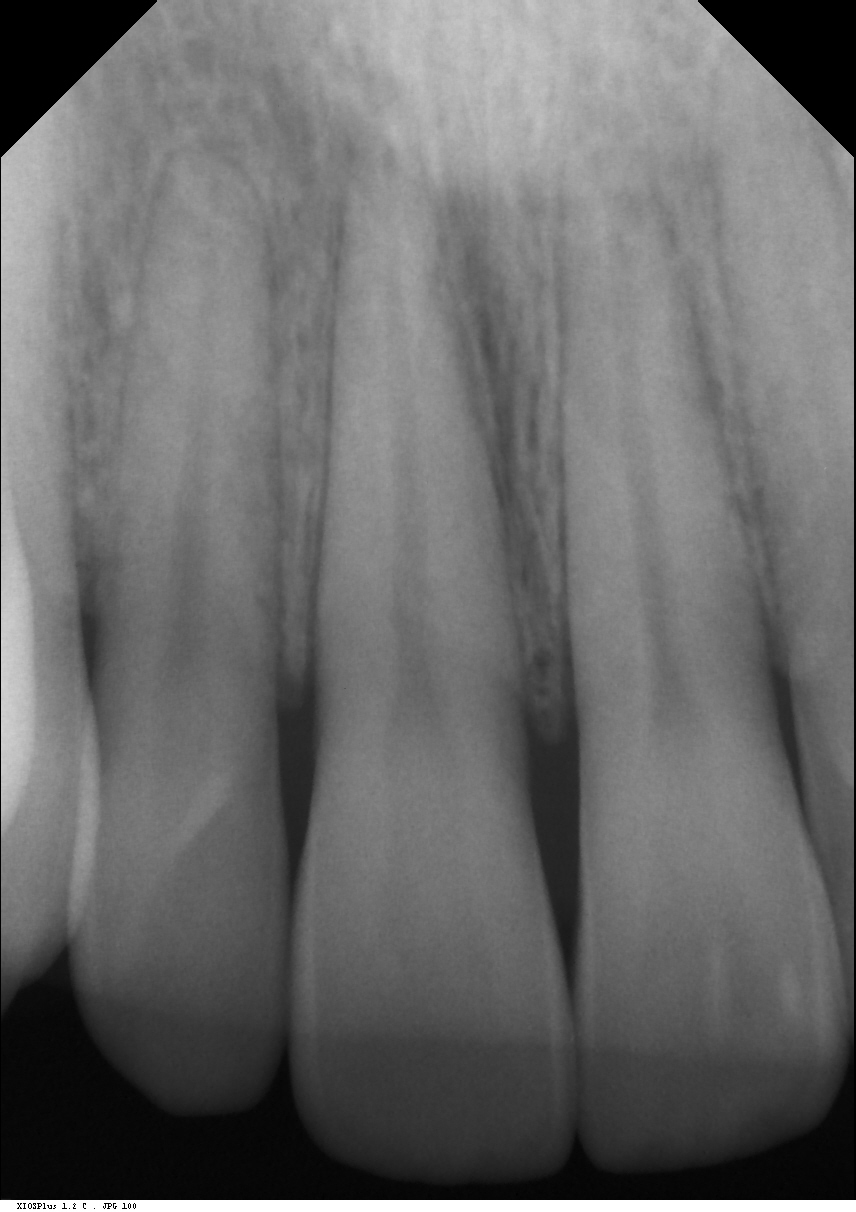

Erst beim letzten Kontrollbesuch am 11.03 konnte im Kleinbildröntgen ein geringgradiger Schatten / eine Entzündung festgestellt werden (siehe Bilder), woraufhin mir eine Wurzelbehandlung empfohlen wurde.

Zu dieser möchte ich allerdings erst dann greifen, wenn kein Zweifel mehr daran besteht, dass sich die Zähne nicht mehr von selbst erholen können, d.h. sie wirklich devital sind.

wirkt röntgenologisch “normal” – zudem wenn der kälte test positiv ist, wieso wb?